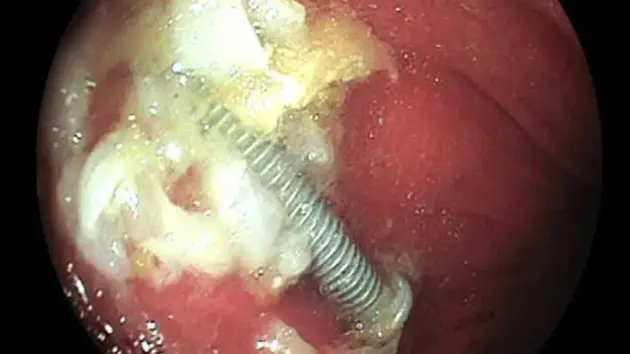

Bệnh nhi được thăm khám, chụp X-quang, siêu âm và xác định chính xác vị trí dị vật nằm trong dạ dày. Trong quá trình gắp dị vật, ê-kíp gặp nhiều khó khăn do dị vật trơn, tròn, lại kèm theo bã thức ăn. Sau 15 phút nỗ lực xử lý, ê-kíp nội soi đã gắp thành công một chiếc đinh vít xoắn dài 5cm từ dạ dày của bệnh nhi. Hiện bệnh nhi được về nhà, tình trạng sức khỏe bình thường.